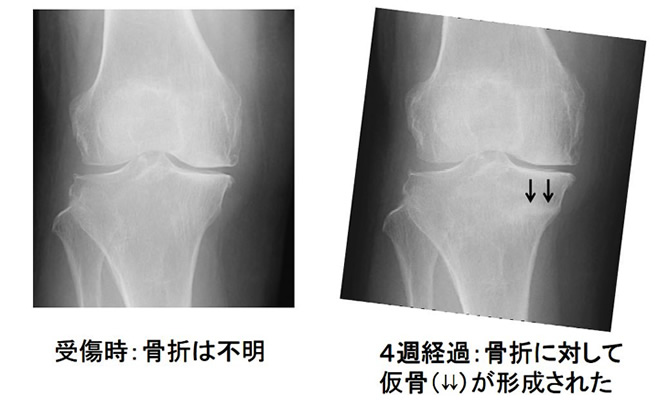

転倒なく通常の歩行で膝痛が生じた症例(脛骨不全骨折)